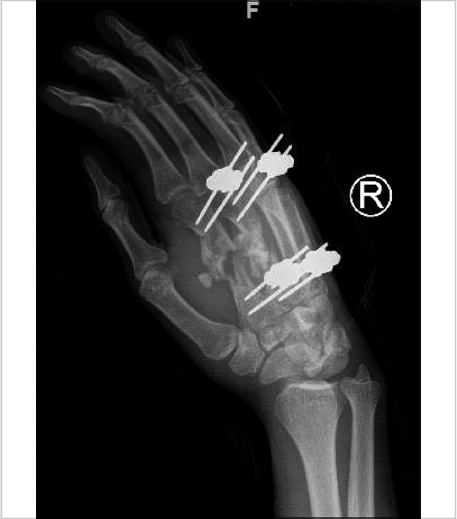

Noncomminuted, displaced fractures that constitute more than 25% ofthe articular surface or exhibit more than 1 mm of articular step-off are treated operatively with K-wires and immobilization. Comminuted fractures require fixation with multiple K-wires or cerclage wires. Unstable reductions may require immobilization for 2 to 3 weeks before range-of-motion exercises are initiated. Skeletal traction or external fixation (► Fig. 38.1, ► Fig. 38.2, ► Fig. 38.3) may be needed if there are associated comminuted fractures of the adjacent base of the proximal phalanx. For open comminuted head fractures, especially fractures with bone loss, prosthetic arthroplasty is a reasonable alternative.